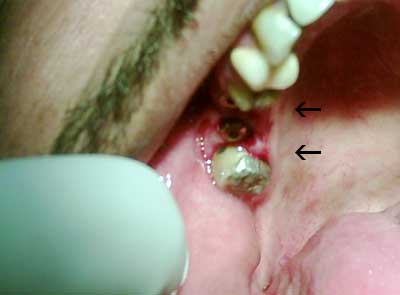

كنت قد أخذت منك أذن في عرض بعض الصور التي صورتها خلال زراعة الأسنان أرجوا أن تنال إعجابك

الزرعات في الفك السفلي إنظر إتجاه الأسهم

الزرعات في الفك العلوي إنظر أتجاه الأسهم